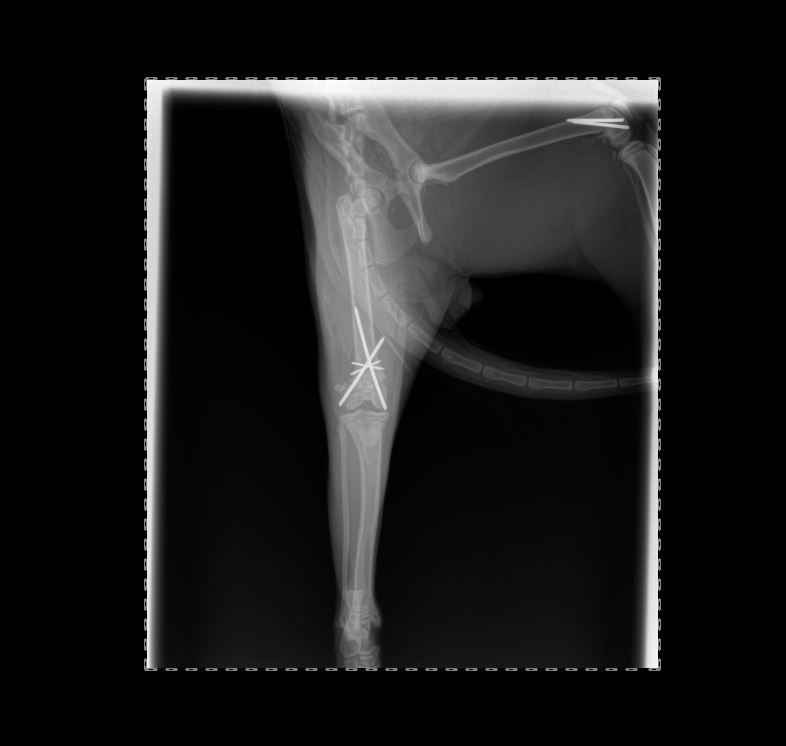

Chirurgies orthopediques:

-réduction des fractures (pose divers implants plaques broches etc),

-rupture du ligament croisé (prothèse ligamentaire)

Pose implant plaque DCP

Pose broche en "X" fracture femur en "Salter"